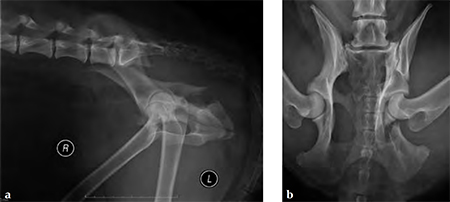

A 4-year-old Gordon setter suffered a road traffic accident and sustained multiple pelvic fractures.

(Case provided by Michael Kowaleski, North Grafton, USA)

A 7-hole 3.5 mm LC-DCP was applied and two screws were inserted into the sacral body to improve fixation strength in the cranial ilial segment. This bone is quite thin thus note that the screws #1 and #2 are quite short, screws #3 and #4 are the sacral screws and are much longer; the fracture is between screws #4 and #5 (see figure 4a-b)). The opacity on midline in the x-rays is a urinary catheter.